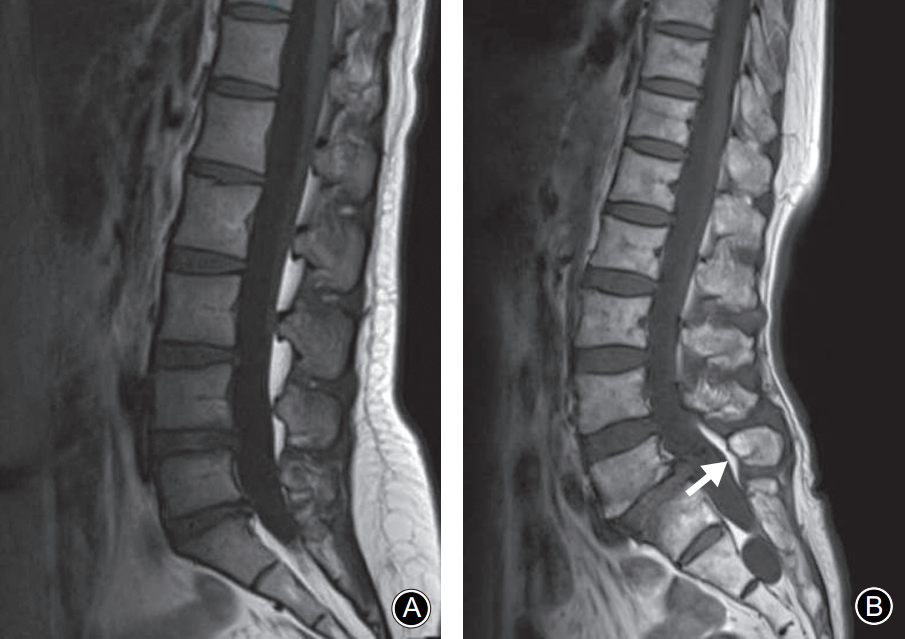

在峡部裂继发的椎体滑脱患者中MRI正中矢状面TIWI示棘突基底部与硬膜之间会出现脂肪的异常增多沉积,且椎体滑脱越严重脂肪增多也越明显。而在尚未出现椎体滑脱的隐匿性峡部裂患者中是否也存在上述脂肪增多的影像学表现呢?最近,一项回顾性研究发现棘突基底部与硬膜之间的脂肪沉积征对隐匿性腰椎峡部裂的诊断有一定的特异性,有助于早期诊断峡部裂。

腰椎MRI正中矢状面 T1WI。A:棘突基底部和硬膜之间未见脂肪沉积;B:L5棘突基底部与硬膜之间可见线状脂肪高信号带(箭头示)

L5椎弓峡部裂典型病例一:男,32岁。A,B: 腰椎正位侧位X线片示无明显椎弓峡部裂征象; C: 腰椎 MRI正中矢状面T1WI示L5棘突基底部与硬膜之间出现脂肪高信号带(箭头示); D: 腰椎CT矢状面重建示L5椎弓峡部骨质不连(箭头示)。

L5椎弓峡部裂典型病例二:男,35岁。A,B: 腰椎正位侧位X线片均无明显椎弓峡部裂征象; C: 腰椎MRI正中矢状面T1WI示L5棘突基底部与硬膜之间出现脂肪高信号带(箭头示); D: 腰椎CT矢状面重建示L5椎弓峡部骨质不连,裂隙较细(箭头示)。